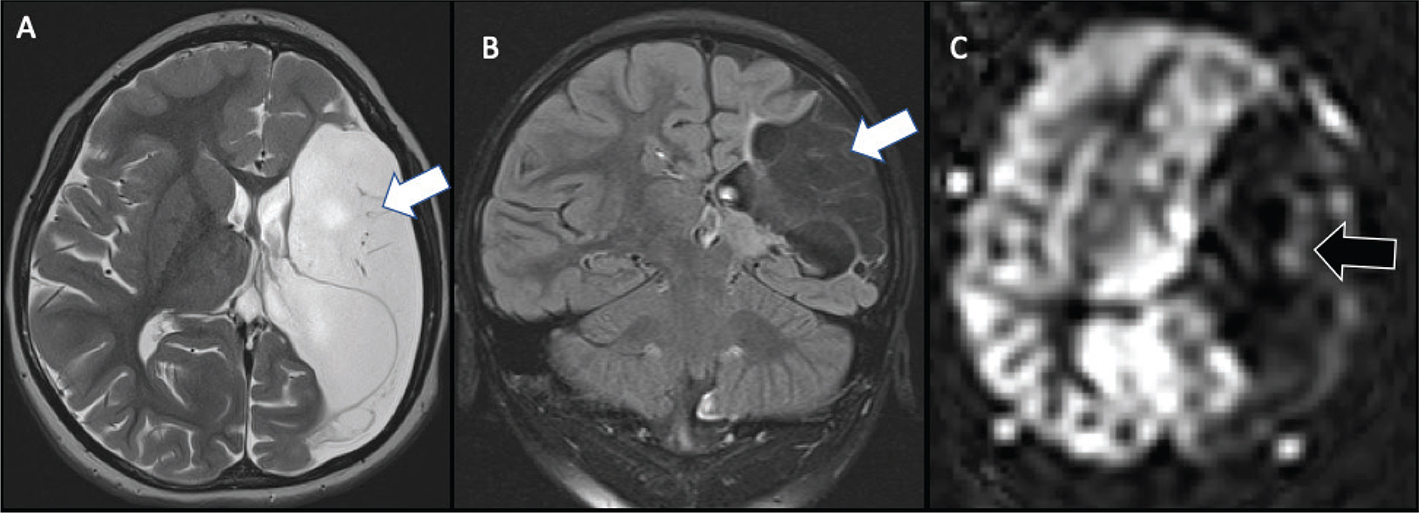

The chronic stage (beginning by 3 weeks) is characterized by volume loss and varying degrees of gliosis. The final appearance of the infarct is related to the timing of insult, the maturity of the infarcted brain, and the degree of astrocytic response to injury, and may span from none (infarct earlier in gestation) to mild (infarct later in gestation and early prenatal period). If injury occurs before 20 weeks of gestation, schizencephaly will often develop, with the cleft lined by dysplastic gray matter. Porencephaly results when the insult occurs between approximately 20 and 24 weeks from liquefactive necrosis, appearing as a smooth-walled, fluid-filled cavity isointense to CSF that may or may not communicate with the ventricular system. The surrounding white matter typically demonstrates normal signal. Encephalomalacia and gliosis results when the insult occurs in the late second trimester and onward, as the brain is able to mount an astrocytic response to injury, and demonstrates surrounding parenchymal signal abnormality, best depicted on FLAIR (Figure 6).

Fig 6

Figure 6. Presumed perinatal ischemic stroke (PPIS). A 10-month-old boy presented with early hand preference and medically refractory epilepsy. Axial T2-weighted (A) and coronal FLAIR (B) images demonstrate chronic infarction with liquefactive changes in the left MCA territory (white arrow) suggesting early injury, with associated decreased perfusion (black arrow) on ASL (C). Case courtesy of Dr. Tamara Feygin, Department of Radiology, Children’s Hospital of Philadelphia.